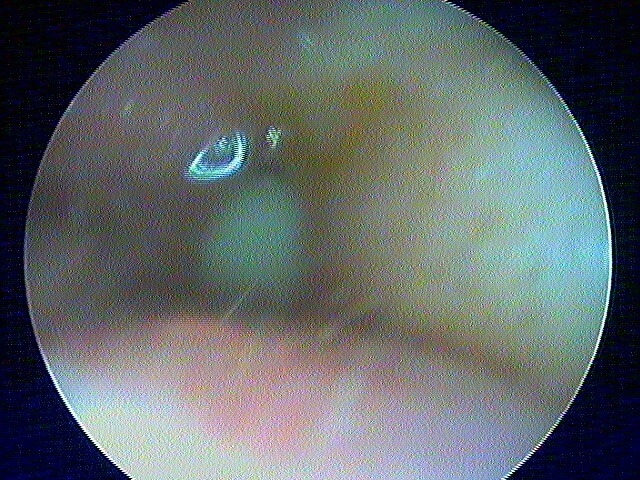

Et la mise en place d'aérateur de type T-tube ici:

Parfois on retrouve l'aérateur englobé, sans conséquence: